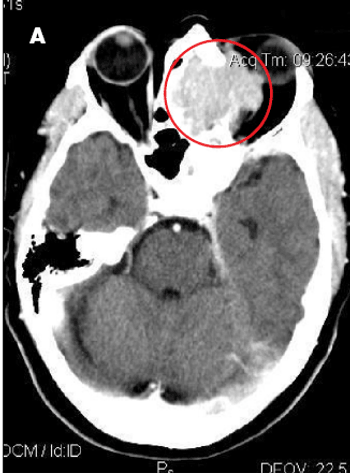

A 26-year-old woman at 30 weeks’ gestation presented to the emergency department with a throbbing frontal headache of 1 month’s duration. She had also had peripheral blurred vision for the past 2 weeks. Acetaminophen initially decreased her pain but was no longer effective. She had had a previous miscarriage.